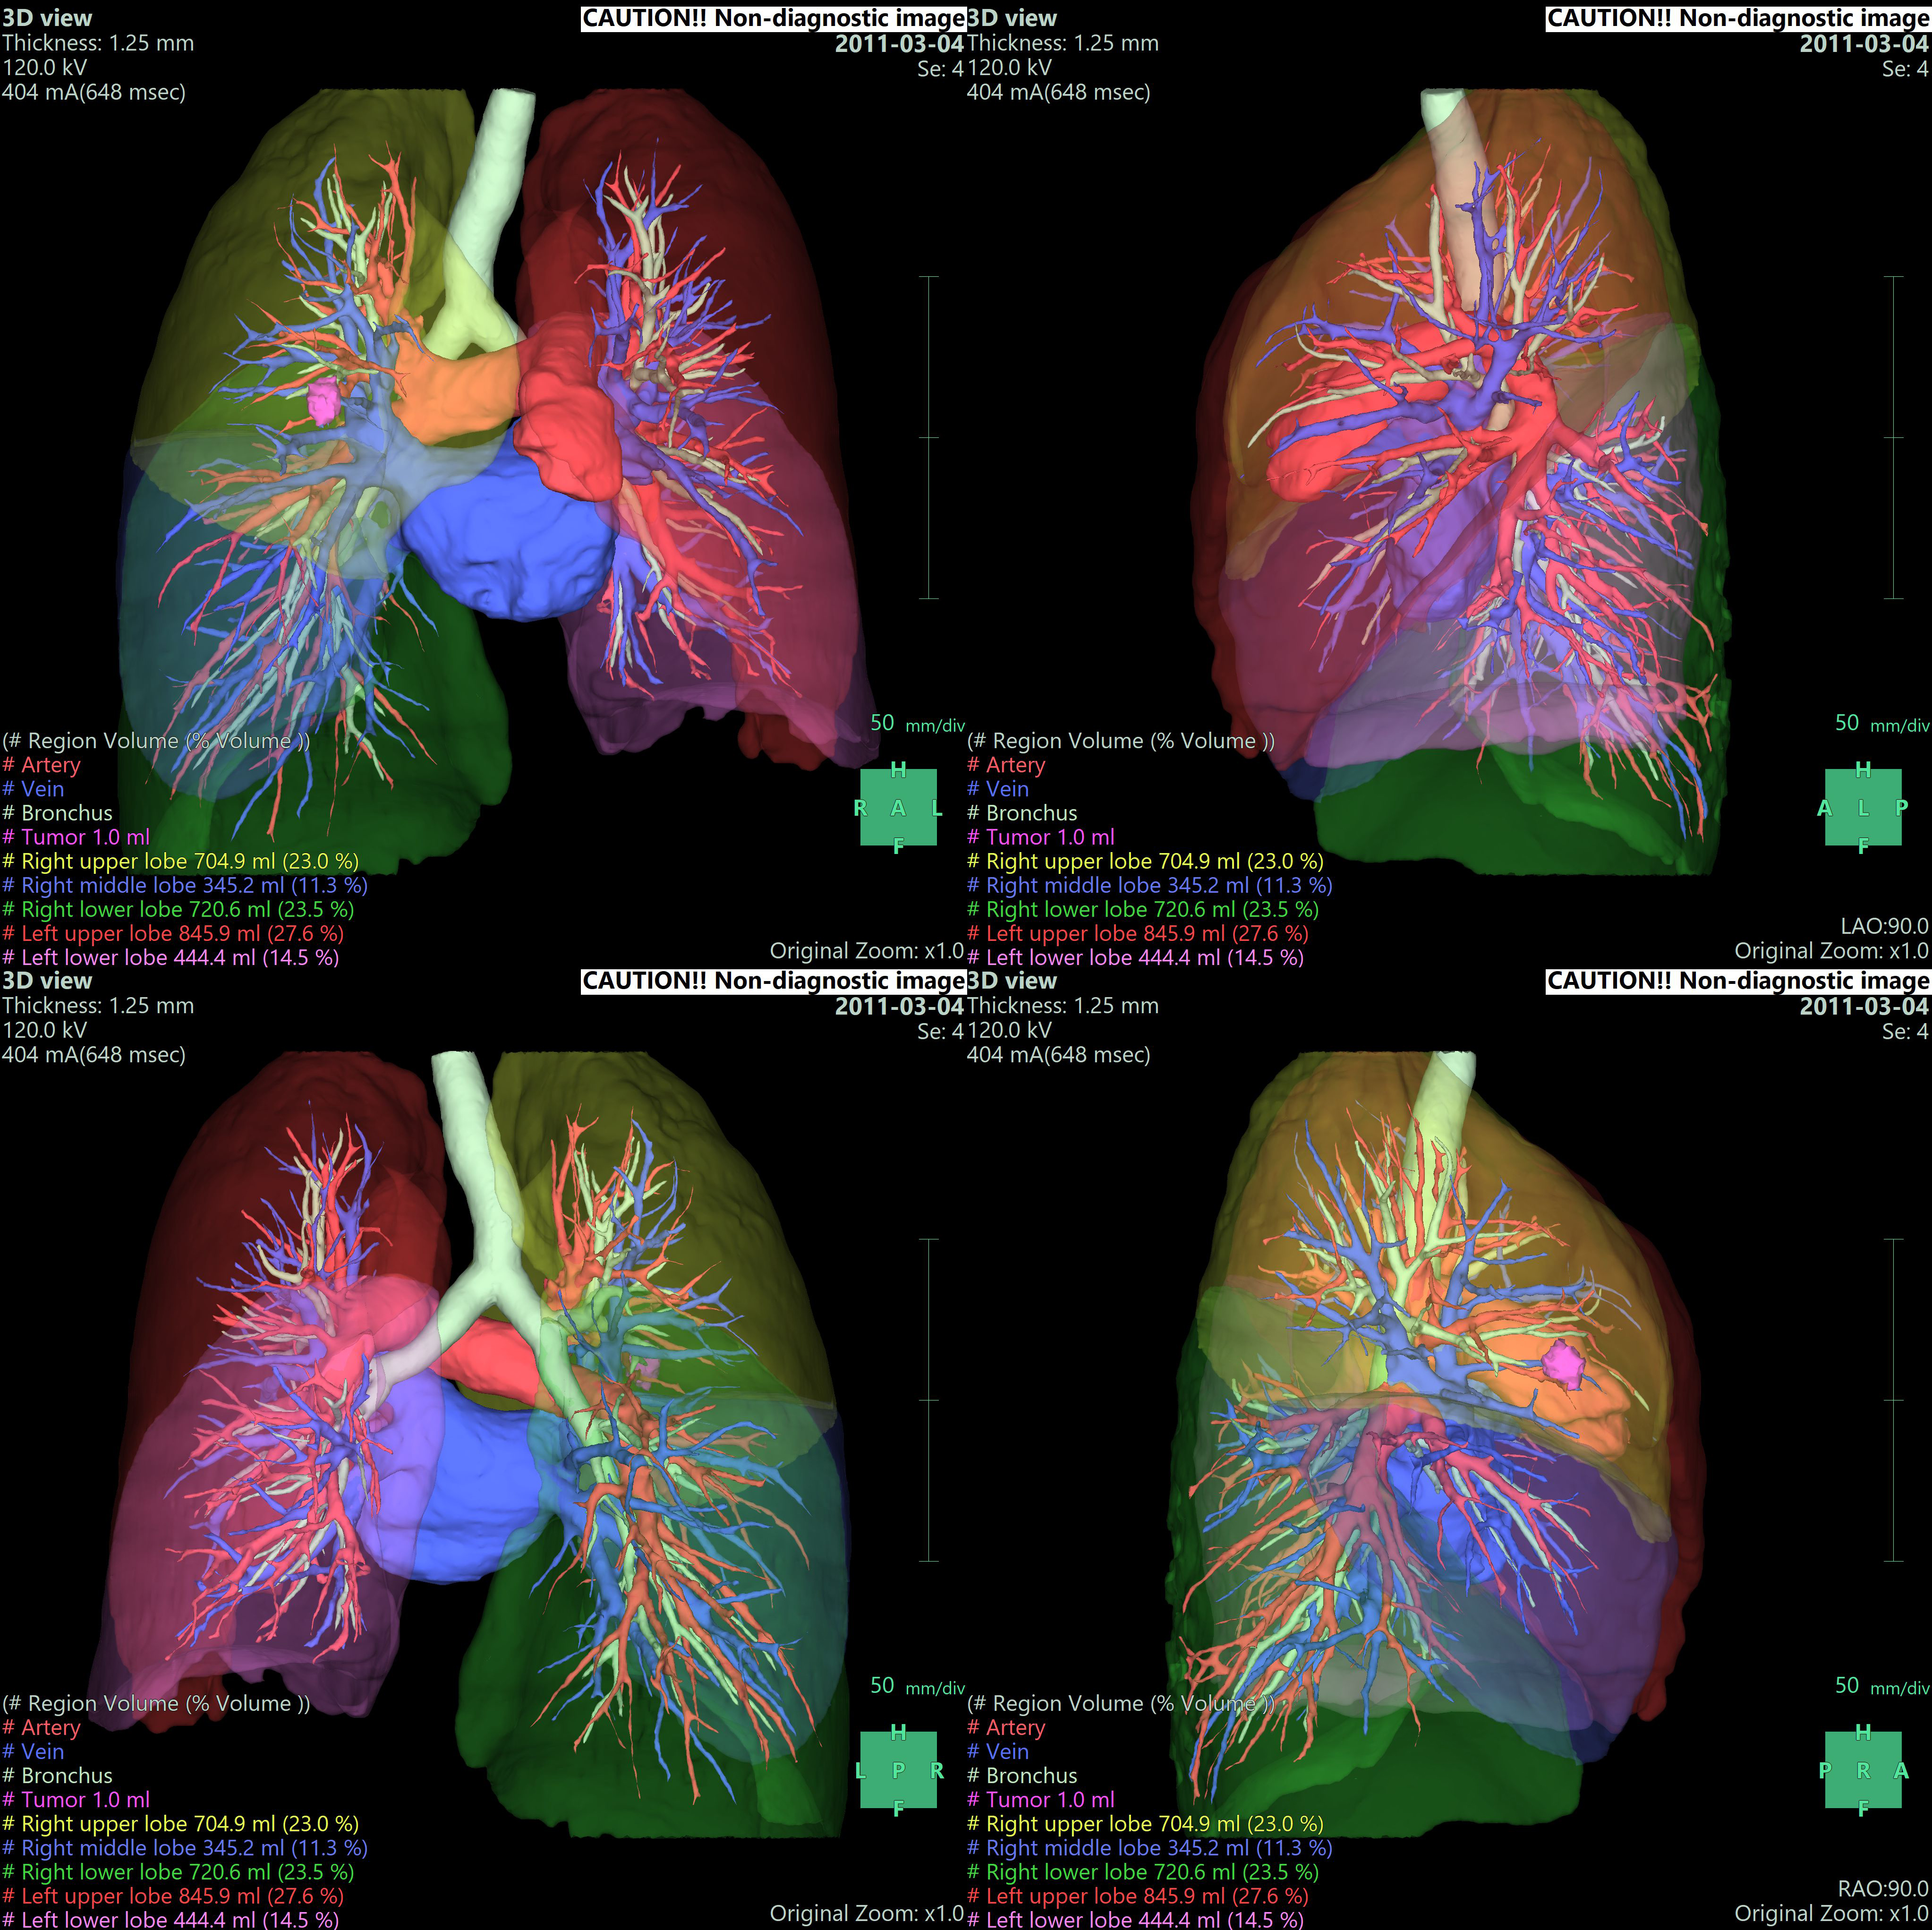

• - 조영 증강된 CT image를 사용하여 Lung, Airway, Vessel, tumor 등을 추출하고 3D로 재구성하고 결과를 관찰할 수 있습니다.

• - 자동으로 Lung의 좌우 및 5개의 Lobe를 분리하고 임의의 bronchus 지점을 기준으로 territory를 분리할 수 있습니다.

• - 임의의 Vascular point에서 territory를 분리하고 절제면, 절제면에서의 Vessel 및 territory의 volume 등을 측정할 수 있습니다.